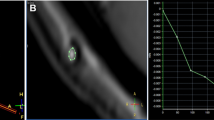

CSF flow quantification through the fenestration

High-resolution axial-oblique cine PC was used for CSF flow quantification through the stoma in group I patients. Axial-oblique true phase images were processed for quantification. Using vendor-supplied standard software (Argus on Leonardo VD10B), a spherical region of interest was placed covering the whole stoma adequately shown on a magnified image where CSF flow and velocity waveforms were generated. The direction of the flow during the diastole and systole through the fenestration was determined. Stroke volume was calculated, as described in the literature [4, 18].

CSF flow through the stoma in group I patients was confirmed qualitatively with demonstration of biphasic flow through the stoma using sagittal and axial-oblique cine PC sequence, where phase images were displayed in closed loop cine format.